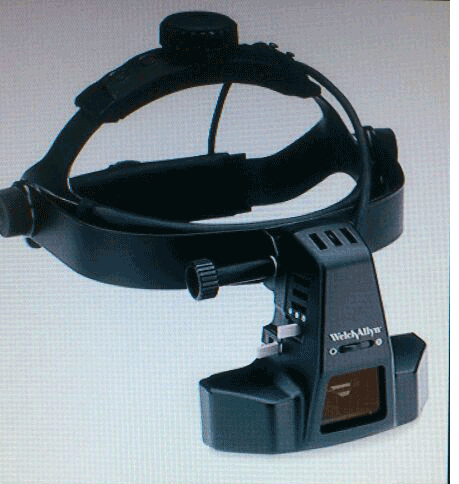

Indirect opthalmoscopy